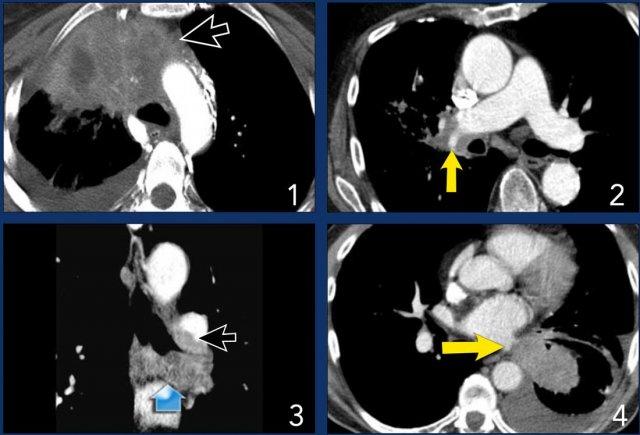

Ví dụ:

- Một khối u T4 điển hình ở thùy trên phổi phải với xâm lấn trung thất.

- Xâm lấn động mạch phổi phải.

- Xâm lấn carina.

- Xâm lấn nhĩ trái.